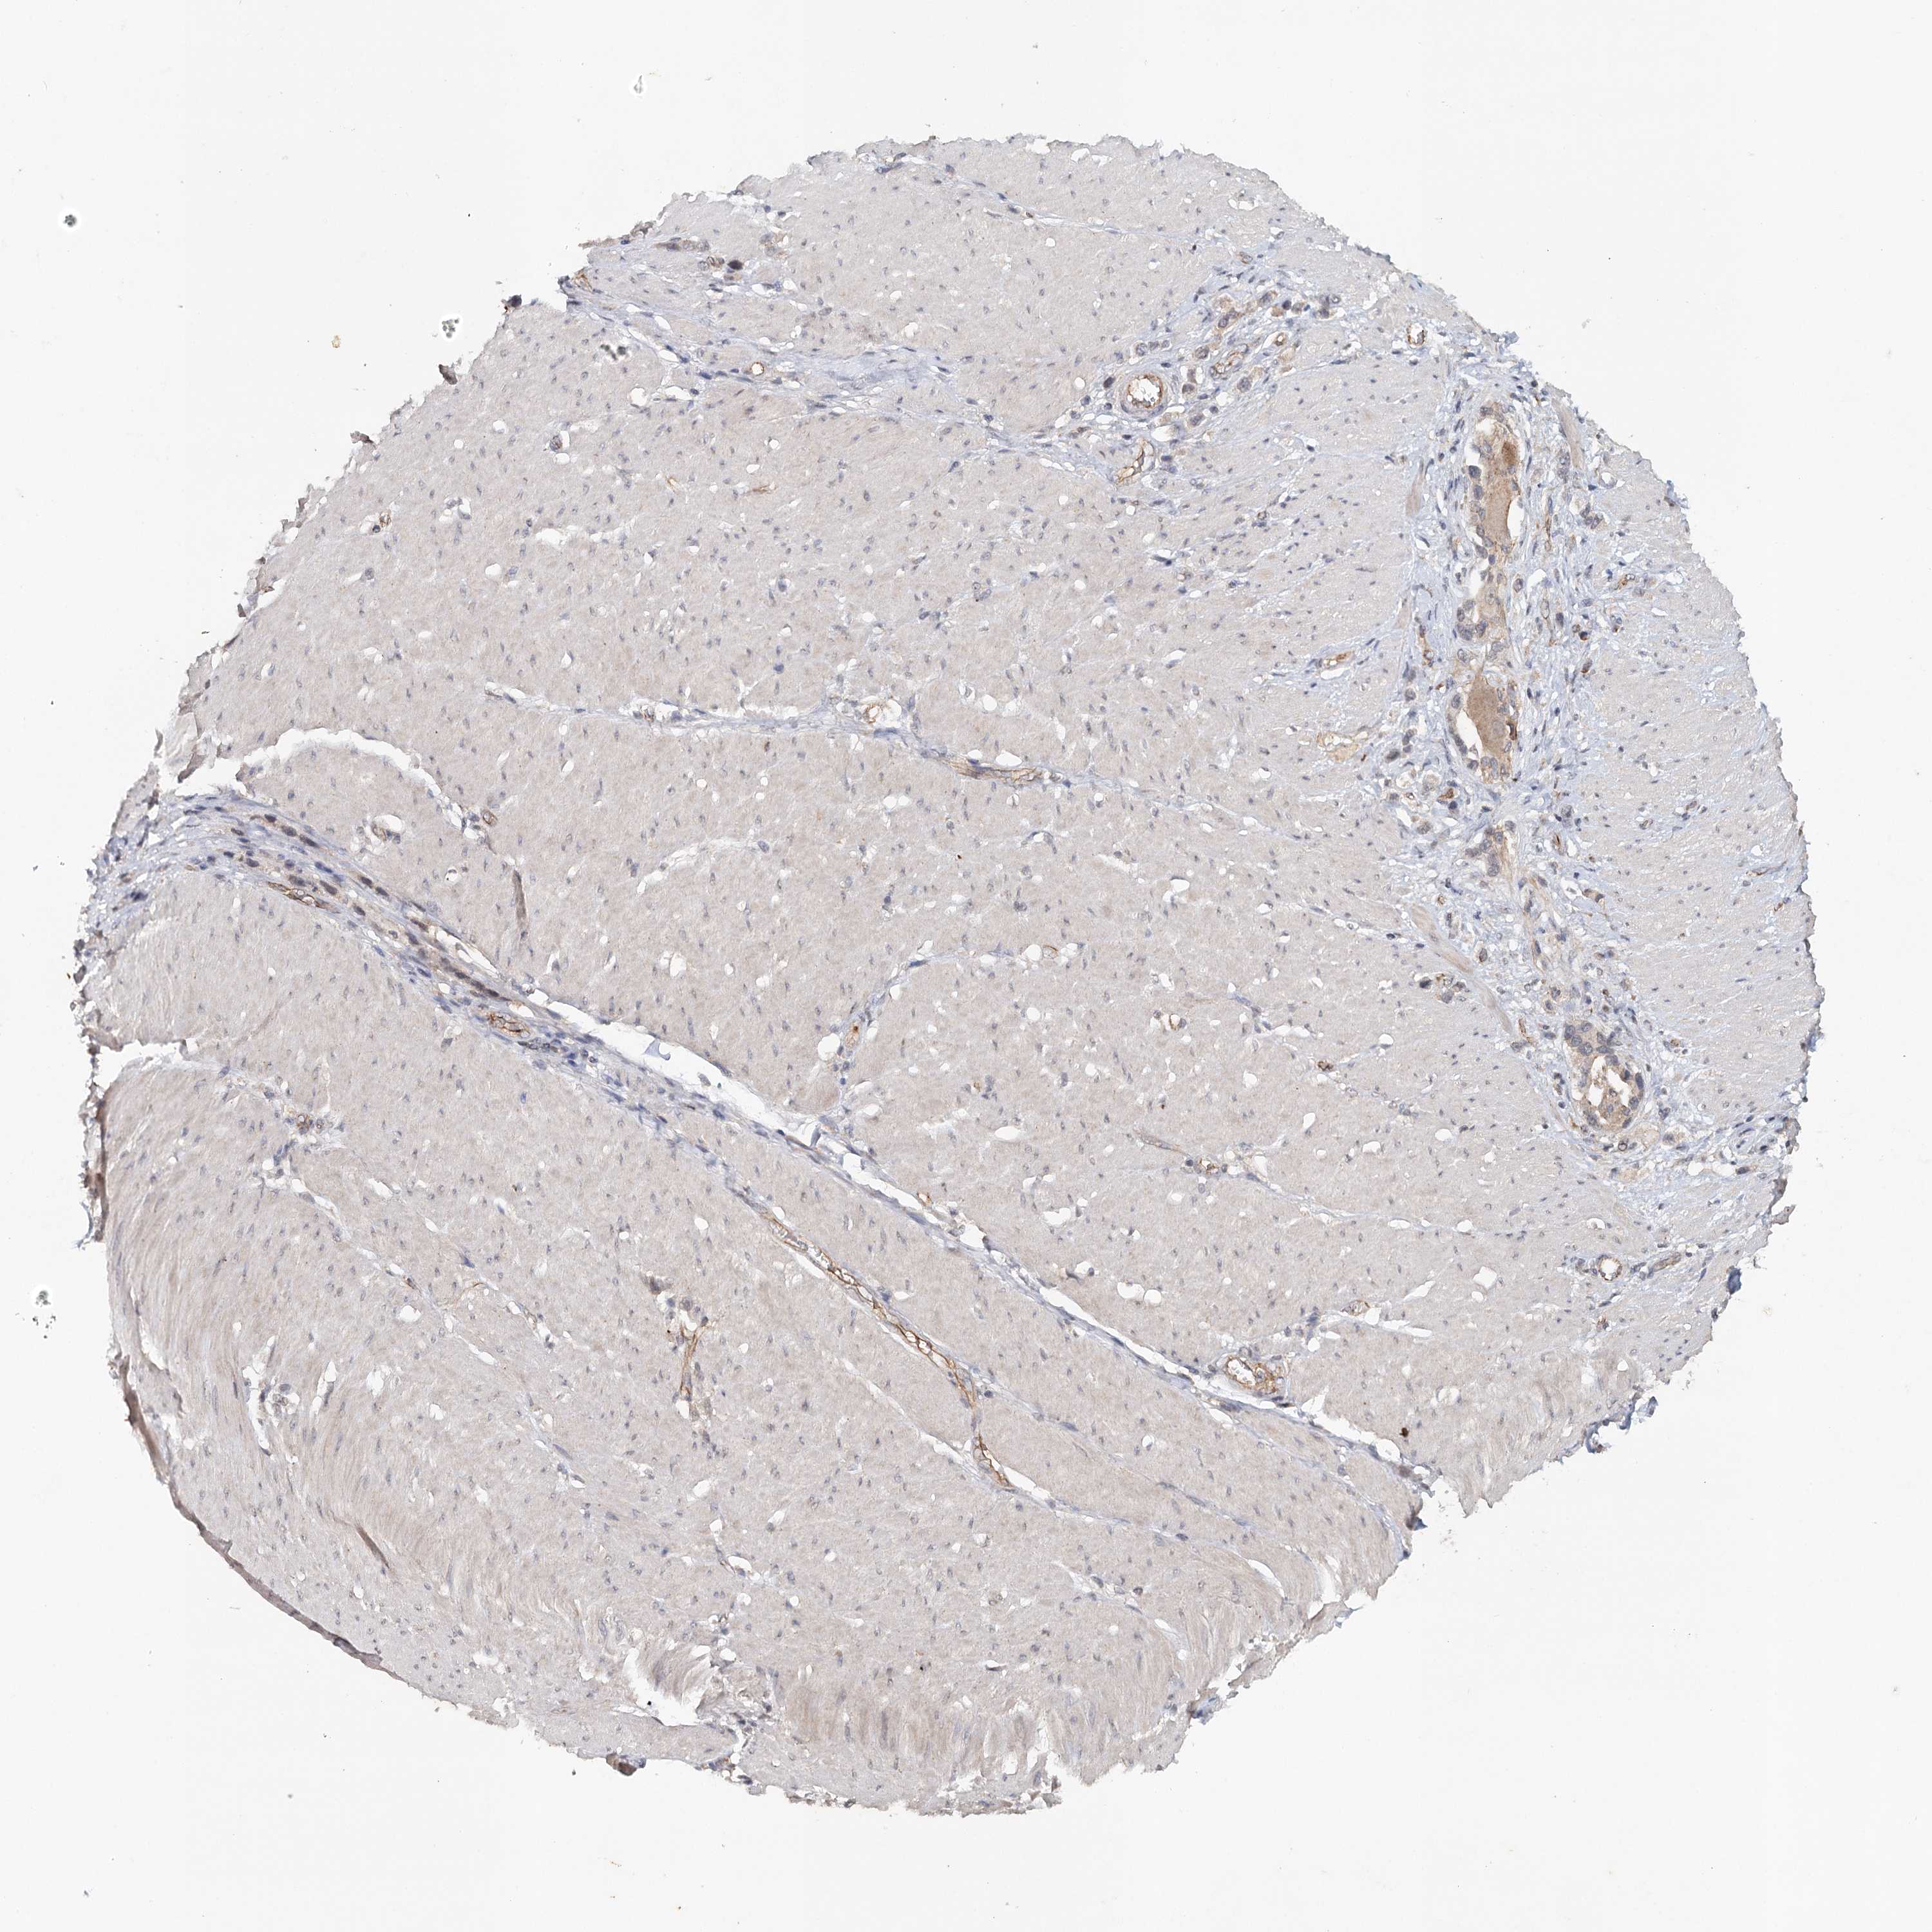

STOMACH CANCER - Protein expressioni

A mouse-over function shows sample information and annotation data. Click on an image to view it in a full screen mode. Samples can be filtered based on level of antibody staining by selecting one or several of the following categories: high, medium, low and not detected. The assay and annotation is described here.

Note that samples used for immunohistochemistry by the Human Protein Atlas do not correspond to samples in the TCGA dataset.

Antibody stainingi

Antibody staining in the annotated cell types in the current human tissue is reported as not detected, low, medium, or high, based on conventional immunohistochemistry profiling in selected tissues. This score is based on the combination of the staining intensity and fraction of stained cells.

Each image is clickable and will lead to virtual microscopy that enables deeper exploration of all samples and also displays staining intensity scores, fraction scores and subcellular localization as well as patient and tissue information for each sample.

Antibody CAB033265

Staining

High

Medium

Low

Not detected

Intensity

Strong

Moderate

Weak

Negative

Quantity

>75%

75%-25%

<25%

None

Location

Nuclear

Cytoplasmic/membranous

Cytoplasmic/membranous,nuclear

Adenocarcinoma, NOS

Adenocarcinoma, High grade